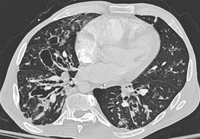

Bronquiectasia

Tomografia computadorizada do tórax com vias aéreas dilatadas e espessadas e um padrão de árvore em brotamento